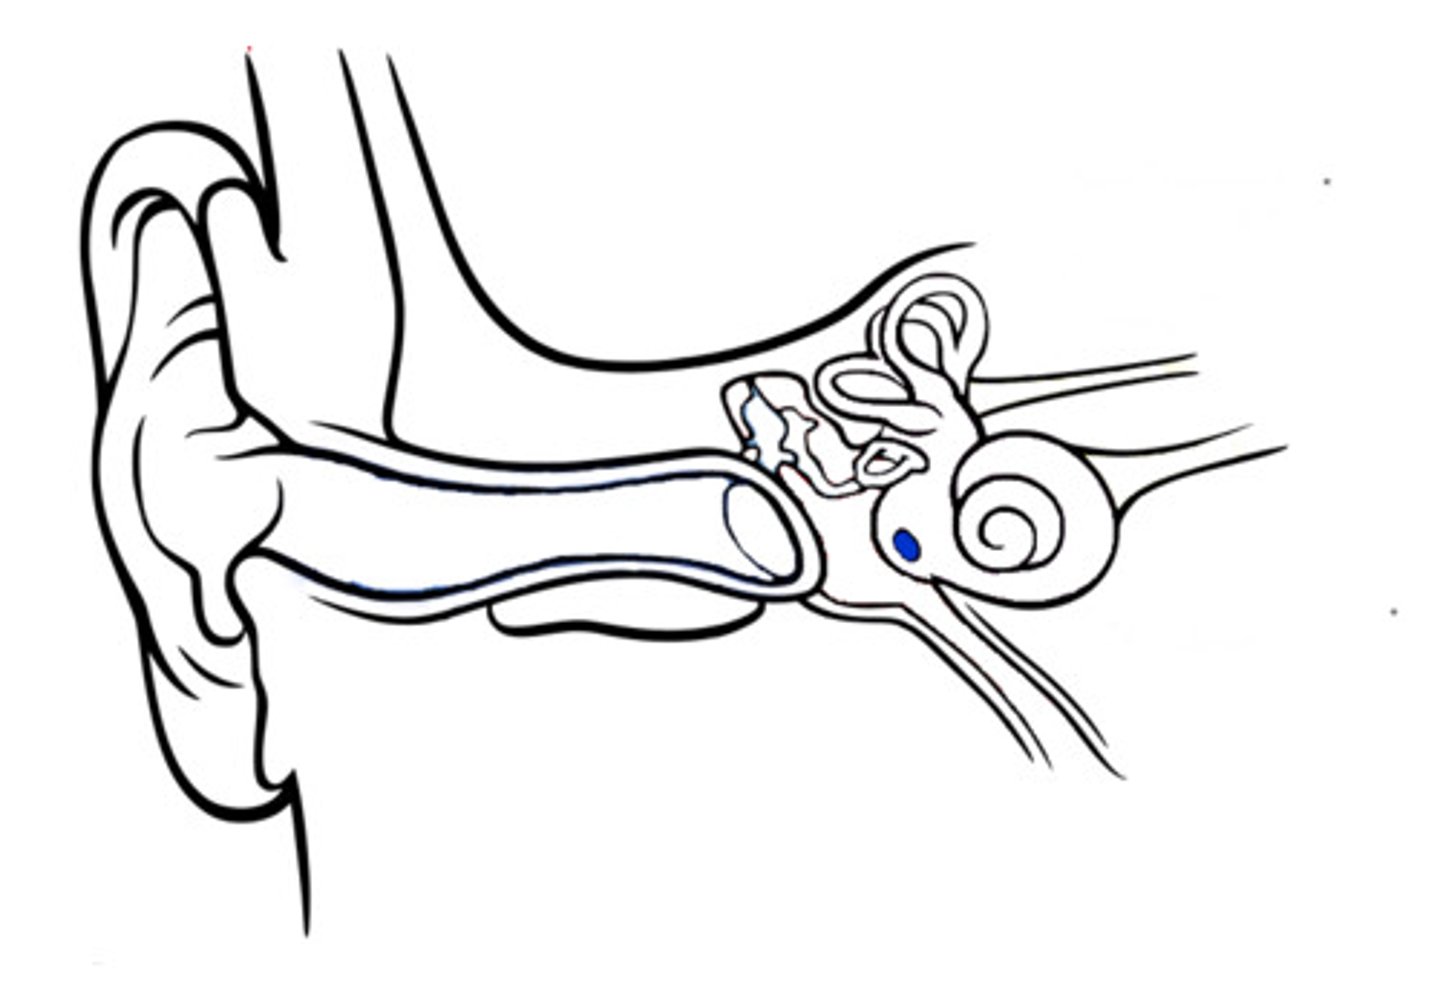

auditory tube

auricle (pinna)

cochlea

cochlear nerve

external auditory canal

incus

labyrinth (osseous + membranous)

(general structure, ignore arrow)

malleus

oval window

round window

scala tympani

section of cochlea

scala vestibuli

section of cochlea

semicircular canals

spiral organ (of corti)

section of cochlea

stapes

temporal bone

tympanic membrane

vestibular nerve

vestibule

vestibulocochlear nerve